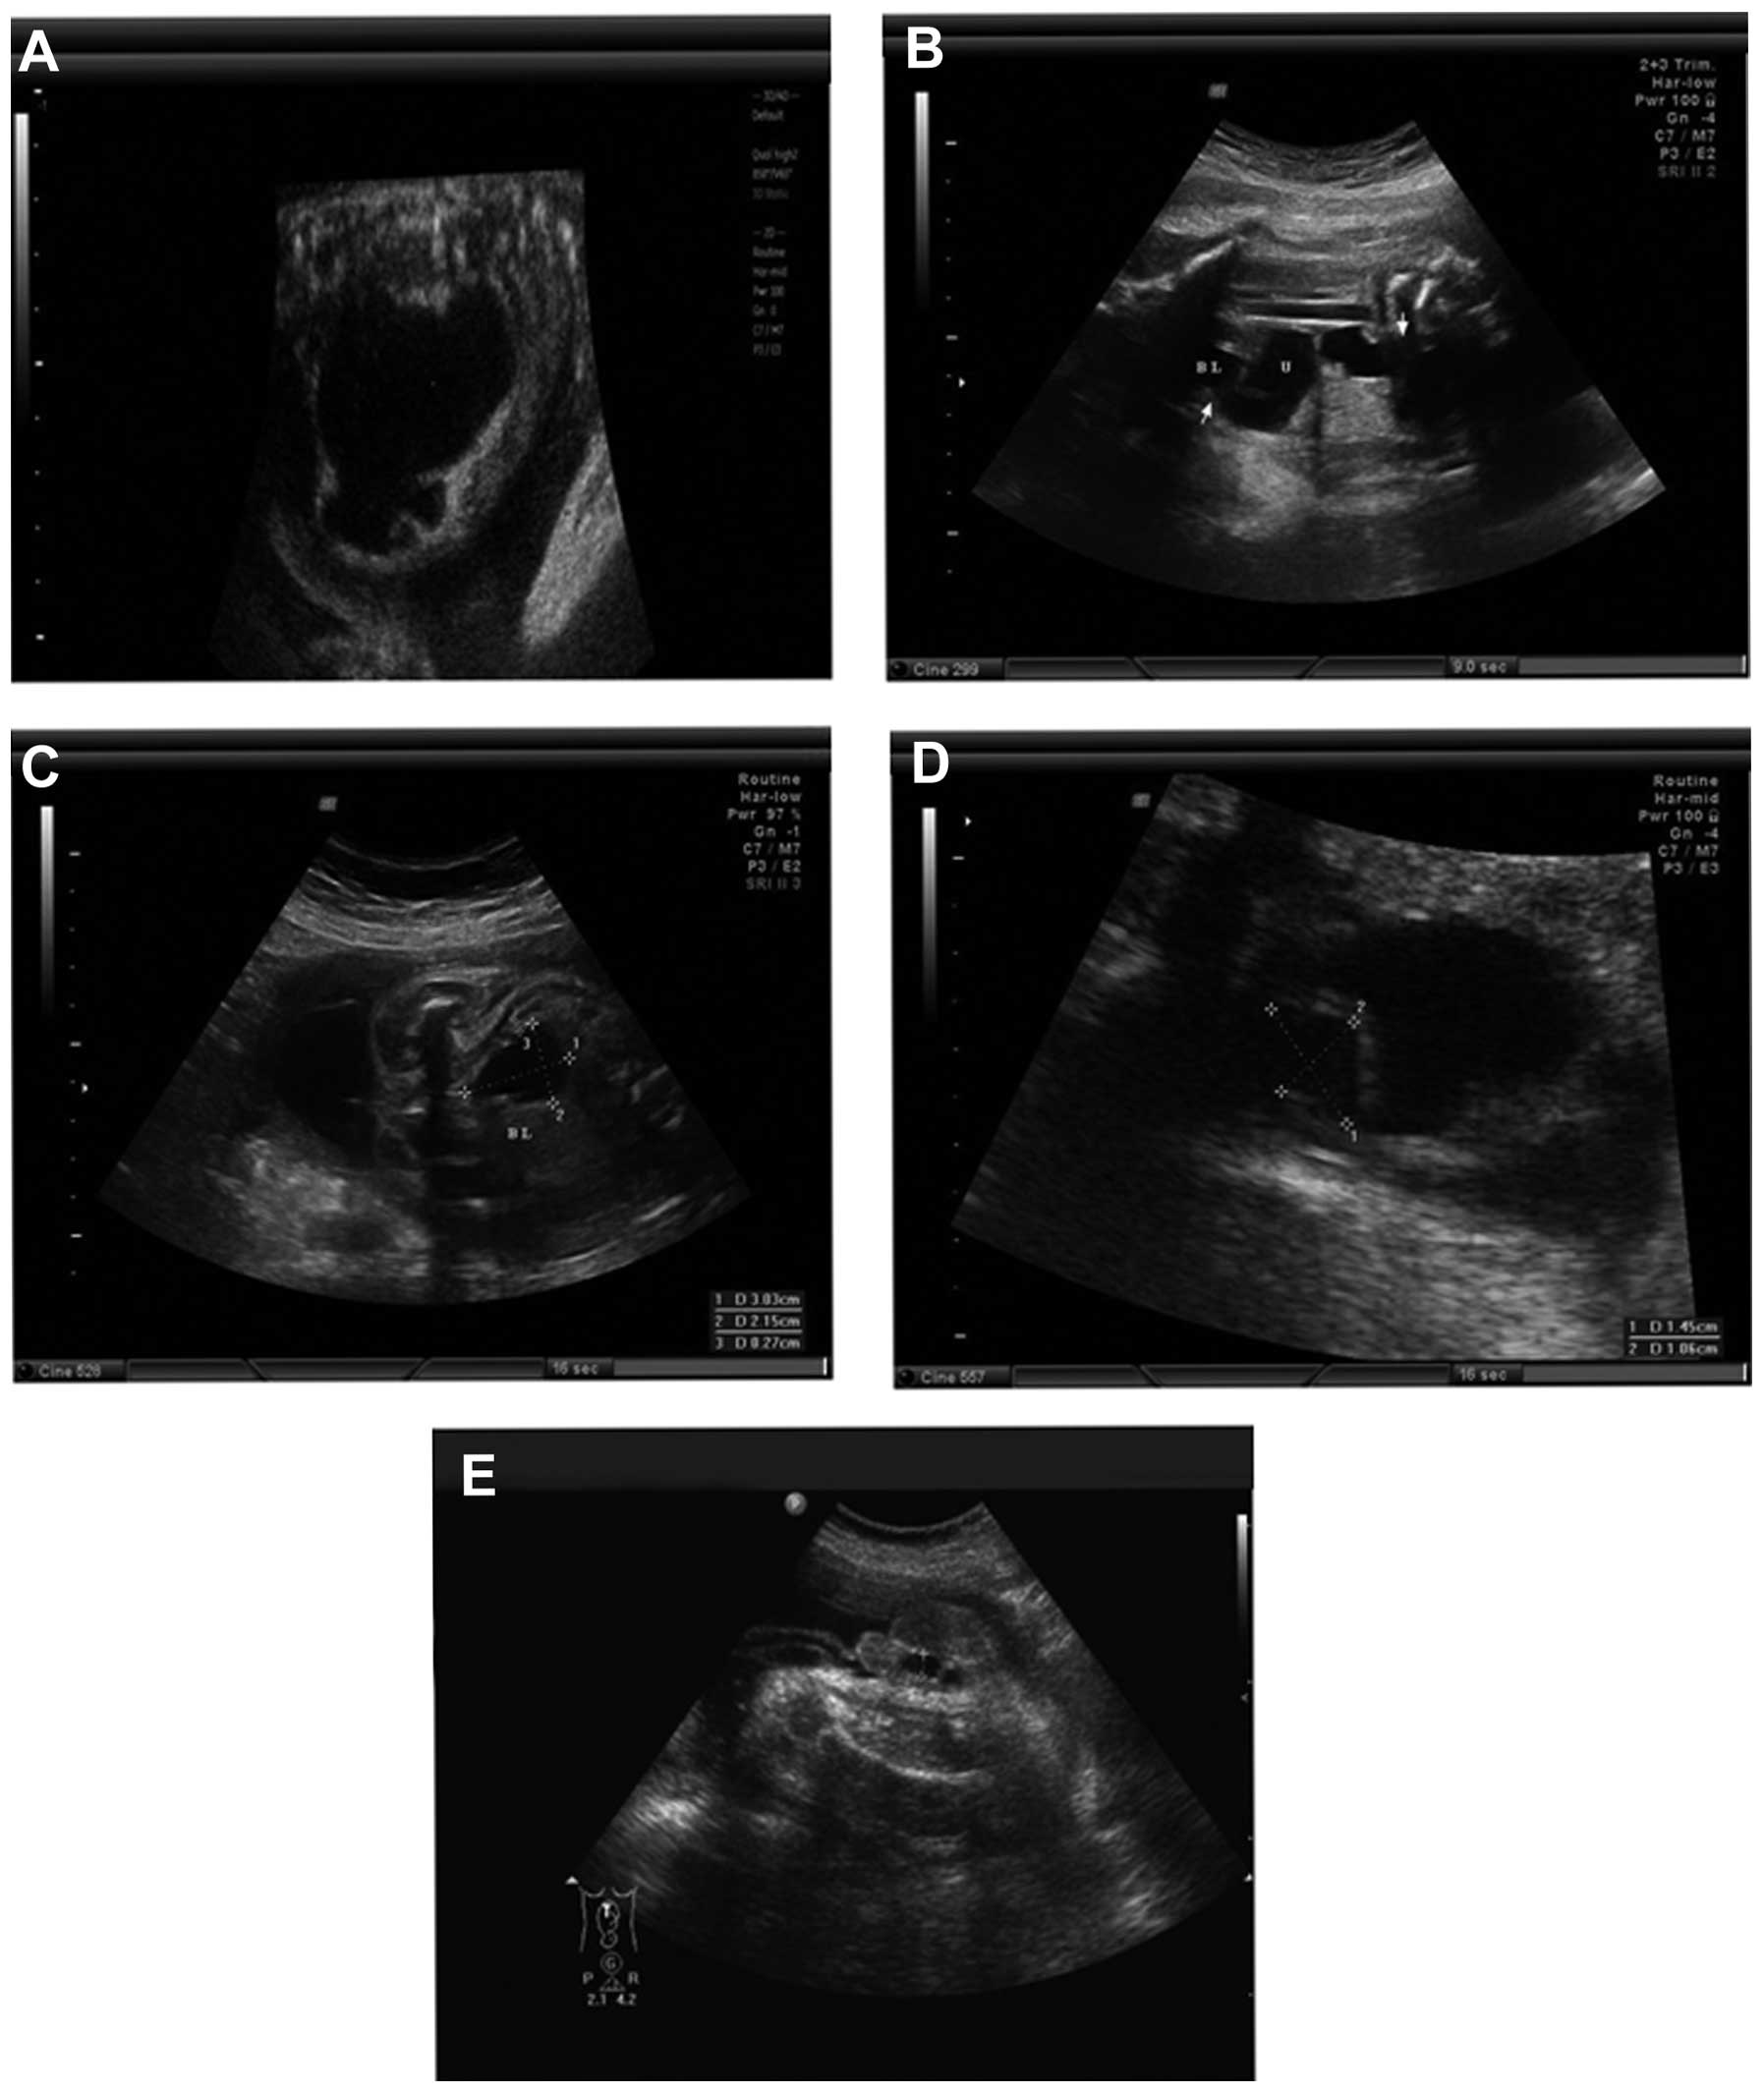

Fetal pyelectasis refers to the prominence of the renal pelvis in utero that is a relatively common finding which in the majority of cases resolves spontaneously. It protects and supports the pelvic contents provides muscle attachment and facilitates the transfer of weight from trunk to legs in standing and to the ischial. A Single-Arm Prospective Study.

It protects and supports the pelvic contents provides muscle attachment and facilitates the transfer of weight from trunk to legs in standing and to the ischial. Trisomy 13 Syndrome is a rare chromosomal disorder in which all or a portion of chromosome 13 appears three times trisomy rather than twice in cells of the body. Radiographic features Ultrasound Antenatal ultrasound. A total of 118 consecutive pregnant women attending for Down syndrome screening at 11- to 136-week were recruited. One theory is that if a blockage develops in the urethra the tube that drains urine from the bladder to the outside of the body urine can build up in the bladder causing pressure and forcing the. However Petit et al. Fetal pyelectasis refers to the prominence of the renal pelvis in utero that is a relatively common finding which in the majority of cases resolves spontaneously.